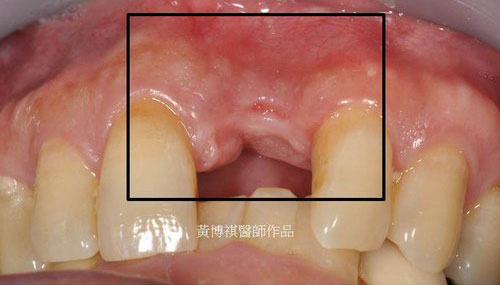

前牙植牙補骨手術範例: |

因為長期缺牙,齒槽骨僅剩0.2mm,使用人工骨粉進行補骨手術後,可見長出了厚厚的新生骨, 足以支撐植入的人工牙根。 |